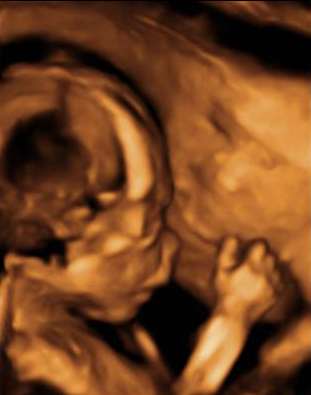

Imagen ecográfica de pie zambo o equinovaro

En la imagen superior se ven los dos pies de un feto, en el lado izquierdo un pie bien orientado con la pierna y en el lado derecho un pie con una desviación anómala, denominada pie equinovaro o zambo.